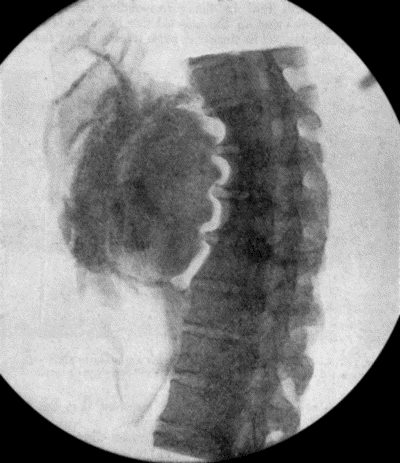

73.Radiogram of Innominate Aneurysm after Treatment by Moore-Corradi method 309

74.Thoracic Aneurysm threatening to rupture 313

75.Innominate Aneurysm in a woman 315